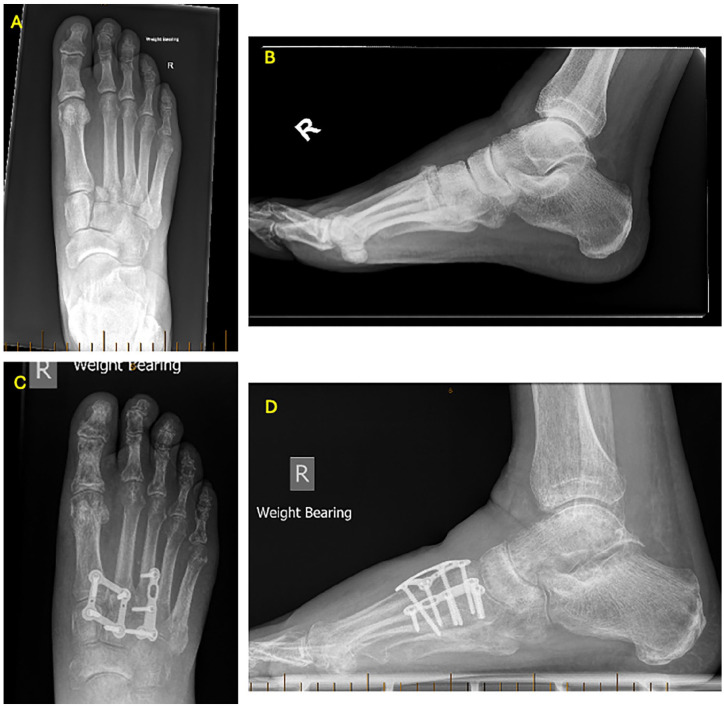

Abstract Image